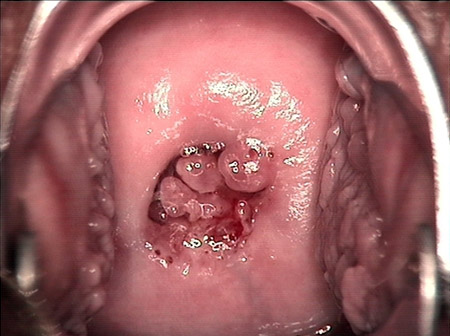

◆宫颈活检:病状较重者,可做宫颈活检以确诊。息肉恶变的病理诊断标准是务必看到全部息肉的形态。》》》推荐阅读:女性有必要定期做妇科体检吗?

◆妇科体检:急性炎症可看见宫颈充血水肿,或糜烂,有脓性分泌液白宫颈管排出,触摸宫颈时会有疼痛感。慢性宫颈炎可看见宫颈有程度不同的糜烂、肥大、息肉、腺体囊肿、外翻等表现,或见宫颈口有脓性分泌液,触诊宫颈较硬。若是宫颈糜烂或息肉,会有接触性出血。